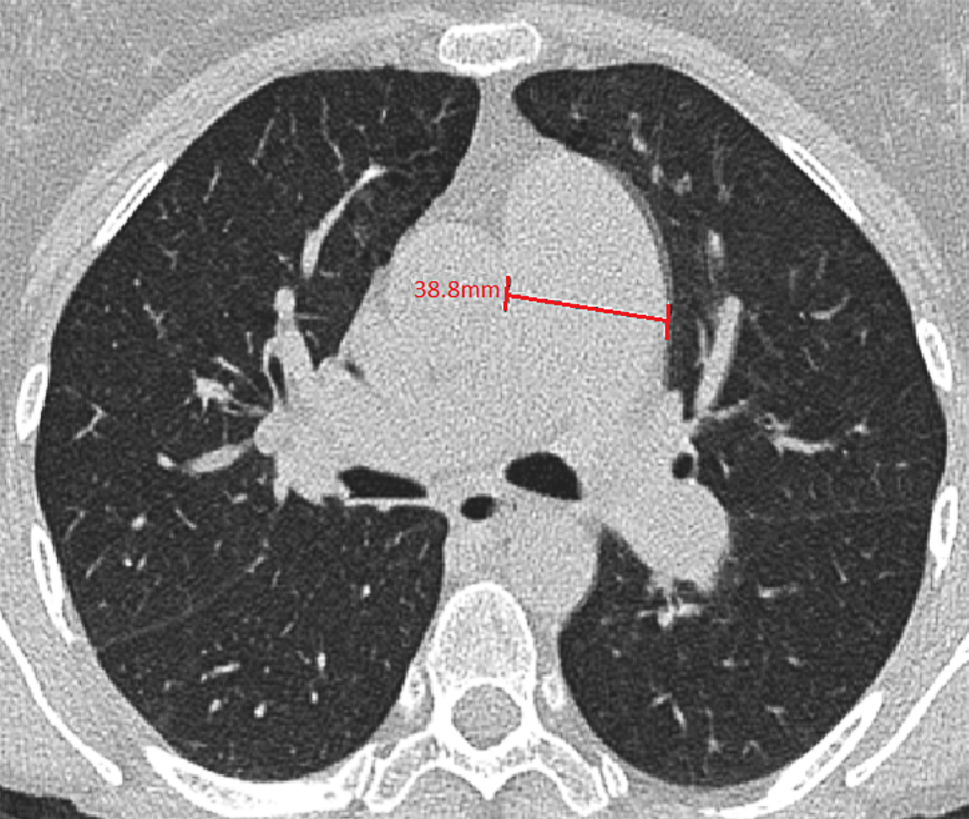

The CT scans were performed for different reasons and therefore not all of them included administration of a contrast medium. The main PA diameter was measured perpendicular to the PA wall in a transversal view at the level of the aorta at which level the right PA was also visible (Fig. 1).

Fig. 1

Example of a measurement of the main pulmonary artery in the transverse plane at the level of the main pulmonary artery on CT scan

PA dilatation was defined as a diameter ≥29 mm for men and ≥27 mm for women, following the upper limit of normal (90th percentile) proposed by the Framingham Heart study [15].